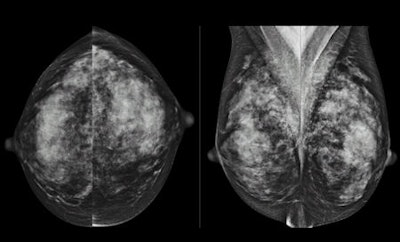

RSNA attendees heard much about breast tissue density as a cancer risk factor -- and what to do about it -- as well as clinical research that points to the efficacy of digital breast tomosynthesis (DBT) as a screening and diagnostic tool.

As for DBT, from posters to scientific sessions, researchers from around the world explored the technology's capabilities.

This research included a study that compared the performance of digital mammography alone to digital mammography plus tomosynthesis in detecting invasive lobular carcinoma, as well as another presentation that addressed the question of whether DBT can influence final BI-RADS assessment categories. Dr. Per Skaane from the University of Oslo presented research that showed that 2D images generated synthetically by a DBT device are clinically comparable to those acquired at conventional mammography -- cutting down on the radiation dose women receive.

In a press conference, Dr. Emily Conant of the University of Pennsylvania shared findings from a study that confirmed again that DBT reduces recall rates and increases cancer detection when it's used for breast cancer screening.

Tomosynthesis is still at an early stage of its development, and there were questions from RSNA attendees about whether focusing on it is really the best direction to take -- especially when there are also exciting developments in technology such as automated breast ultrasound, which doesn't add any additional radiation. Conant acknowledged this issue when she delivered her study findings.

"Tomosynthesis is not the solution to everything," she said. "But the technology is an exciting improvement on what we use routinely."